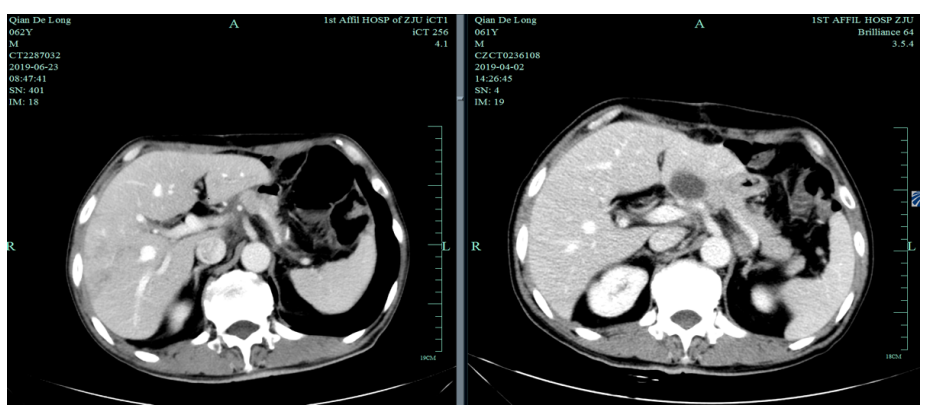

一线化疗疗效评估(2019.6 vs 2019.4):胃癌术后改变。影像评估CR。

由于奥沙利铂8个周期化疗结束,2019-6-26至2019-11-29行S-1+赫赛汀 q3w 8周期联合维持治疗:替吉奥3# BID D1-14、赫赛汀 300mg D1。

影像学评估:胃癌术后改变。持续CR。